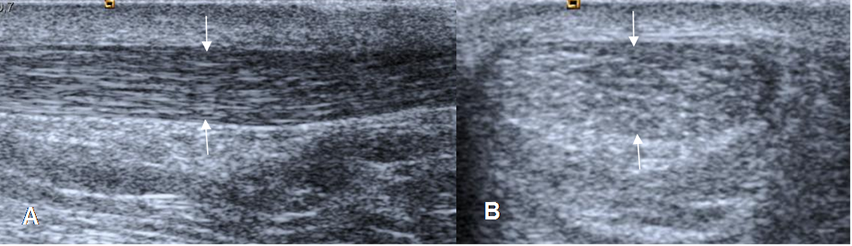

Los tendones normales se aprecian como bandas ecogénicas, con fibras hipoecoicas en su interior. (4). (Fig 3).

Fig 3. Tendón de aquiles normal.

A: Ecografía corte longitudinal y B: corte transversal. Estructura tubular homogénea, con patrón fibrilar.